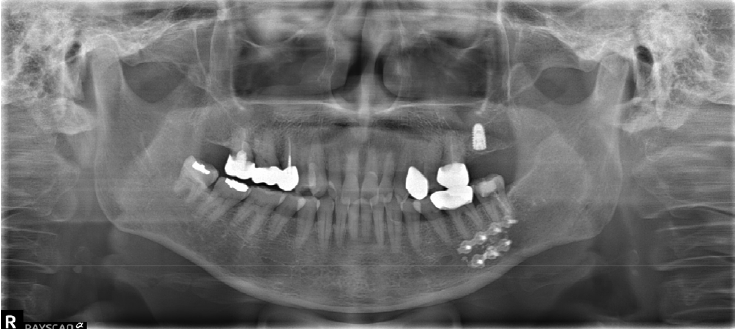

A 63-year-old female presented three days after endodontic treatment of the mandibular left second molar (#37) with symptoms of numbness in the left lower lip and gingiva. A panoramic radiograph and cone-beam computed tomography (CBCT) revealed extrusion of Calcipex II into the mandibular canal (Fig. 1). Initial neurosensory testing demonstrated mild hypoesthesia. She was admitted for foreign body removal and neurorrhaphy under general anesthesia. A post-operative panoramic radiograph confirmed the removal of the foreign body (Fig. 2). Although surgical curettage and neurorrhaphy were performed on the fourth day post-onset, no significant symptom relief was noted at the one- and two-week follow-ups. At the three-month follow-up, she reported persistent numbness with mild neuropathic discomfort but no marked improvement. A follow-up neurosensory exam is scheduled for the six-month check-up.- Case 2

A 41-year-old female reported persistent numbness in the right lower lip and chin following endodontic treatment of the mandibular right second molar (#47). A panoramic radiograph and CBCT revealed extrusion of Calcipex II into the IAN (Fig. 3). She declined surgical intervention and was treated conservatively with mecobalamin and gabapentin. Serial follow-ups at one and three months showed no clinical improvement.- Case 3